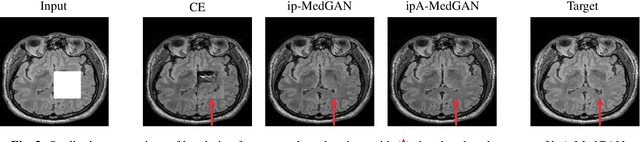

Abstract:Local deformations in medical modalities are common phenomena due to a multitude of factors such as metallic implants or limited field of views in magnetic resonance imaging (MRI). Completion of the missing or distorted regions is of special interest for automatic image analysis frameworks to enhance post-processing tasks such as segmentation or classification. In this work, we propose a new generative framework for medical image inpainting, titled ipA-MedGAN. It bypasses the limitations of previous frameworks by enabling inpainting of arbitrarily shaped regions without a prior localization of the regions of interest. Thorough qualitative and quantitative comparisons with other inpainting and translational approaches have illustrated the superior performance of the proposed framework for the task of brain MR inpainting.